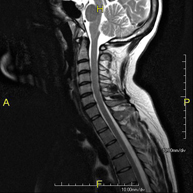

Prova diagnòstica no invasiva que consisteix en l'obtenció d'imatges d'alta definició anatòmica de la columna cervical mitjançant l'ús d'un camp electromagnètic i ones de ràdio (com un emissor i un receptor). No utilitza radiació ionitzant. Indicacions: traumatisme, degeneració de la columna, hèrnies. - RM de columna dorsal

Prova diagnòstica no invasiva que consisteix en l'obtenció d'imatges d'alta definició anatòmica de la columna dorsal mitjançant l'ús d'un camp electromagnètic i ones de ràdio (com un emissor i un receptor). No utilitza radiació ionitzant. Indicacions: traumatisme, problemes degeneratius, hèrnies, tumors. - RM de Columna lumbar

Prova diagnòstica no invasiva que consisteix en l'obtenció d'imatges d'alta definició anatòmica de la columna lumbar i sacre mitjançant l'ús d'un camp electromagnètic i ones de ràdio (amb un emissor i un receptor). No utilitza radiació ionitzant. Indicacions: traumatismes, ciàtica, hèrnies discals, tumors, infeccions - RM Mielografia

Prueba diagnóstica no invasiva que consiste en la obtención de imágenes de alta definición anatómica de la columna cervical mediante el empleo de un campo electromagnético y ondas de radio (con un emisor y un receptor). No utiliza radiación ionizante. Indicaciones: traumatismo, degeneración de la columna, hernias. - RM Columna Dorsal

Prueba diagnóstica no invasiva que consiste en la obtención de imágenes de alta definición anatómica de la columna dorsal mediante el empleo de un campo electromagnético y ondas de radio (con un emisor y un receptor). No utiliza radiación ionizante. Indicaciones: traumatismo, problemas degenerativos, hernias, tumores. - RM Columna Lumbar

Prueba diagnóstica no invasiva que consiste en la obtención de imágenes de alta definición anatómica de la lumbar y sacra mediante el empleo de un campo electromagnético y ondas de radio (con un emisor y un receptor). No utiliza radiación ionizante. Indicaciones: traumatismos, ciática, hernias discales, tumores, infecciones. - RM Sacro-cóccix